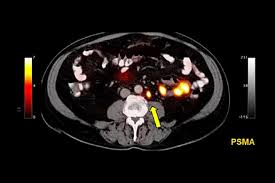

Psma Pet Ct Visualizes Prostate Cancer Recurrence Early Impacts Radiation Therapy from scx2.b-cdn.net A sign that your cancer may have returned is if your psa level has risen by 2ng/ml or more above its lowest level. If cancer is found after treatment, and after a period of time when the cancer couldn't be detected, it's called a cancer recurrence. Twenty to 30 percent of men who have been successfully treated for prostate cancer will experience a relapse more than five years after treatment, even if they have received a. If the psa starts to rise again after it has gone down to zero or close to zero, this may signal that the prostate cancer has returned. The psa test is a very effective way of checking how successful your treatment has been. Prostate cancer metastasis may be suspected if you have specific symptoms such as new lower back pain or elevated liver enzymes. A frequently asked question is 'how can the cancer come back if the prostate has been removed?' the explanation is that, as with any cancer, if cancerous cells migrate out of the organ in which they arose before the organ is removed (or treated with radiotherapy), they can settle and grow elsewhere. But the effect of a.